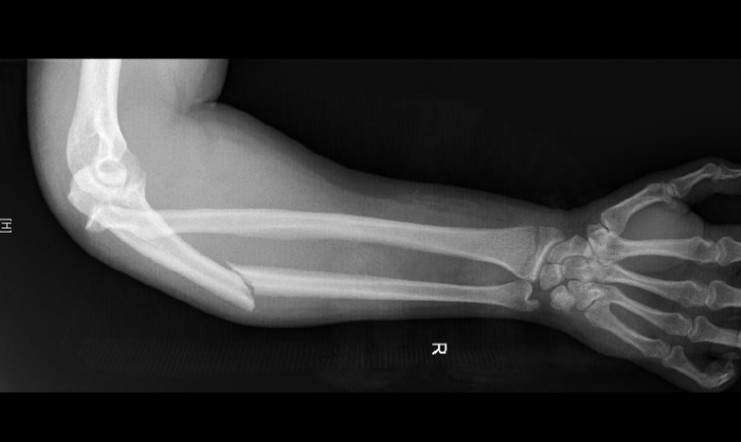

Arm injury

A 35-year-old man presents with a painful right arm after falling from a jet ski.

2024 Term 1 Wk 6 Archived

A 35-year-old man presents with a painful right arm after a fall from his jet ski 1 hour prior to …

2025 Term 2 Wk 5 Archived